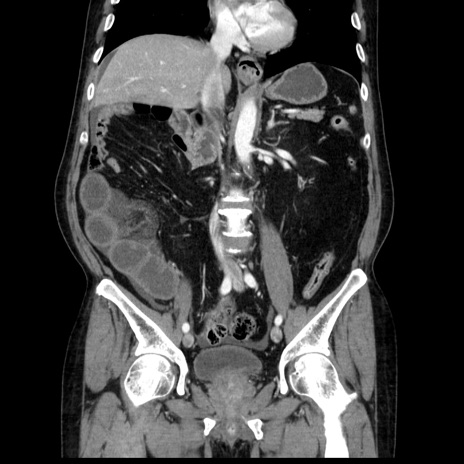

症例30(冠状断像)

【症例】80歳代男性

【主訴】臍周囲痛

【現病歴】約6時間前から臍下部痛が出現。次第に腹部膨隆・背部痛も生じてきたため来院。背部痛の場所は変化しない。

【身体所見】意識清明、BT 36.3℃、BP  131/87mmHg、P 87bpm、SpO2 100%(RA)、臍周囲自発痛・圧痛あり、反跳痛なし、自発痛部位に一致して板状硬あり、腹部膨隆、腸雑音減弱、CVA tenderness両側陰性。

【データ】WBC 19600、CRP 0.33